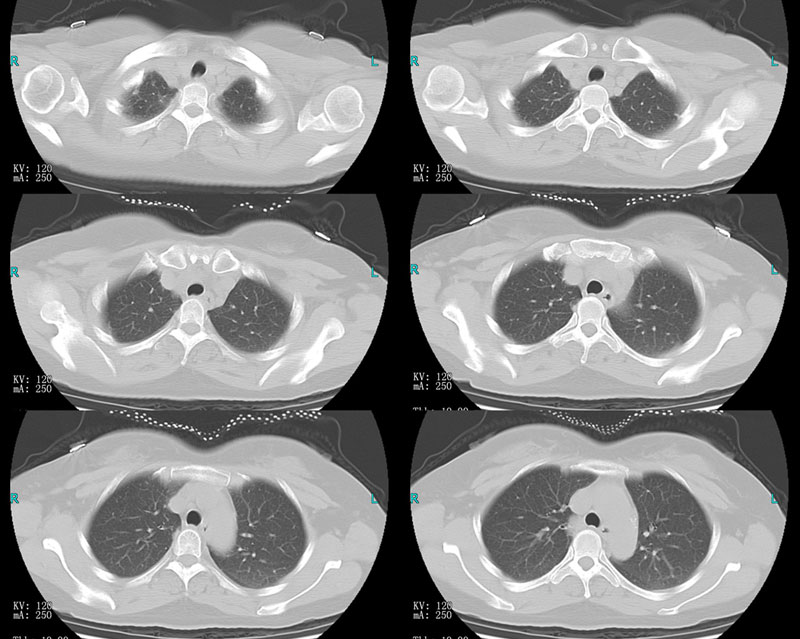

CL2692:支气管扩张

女性,55岁。 主诉:咳嗽气促9天。 现病史:患者于9天前出现恶寒发热,咳嗽咳痰,色黄质粘,气促,伴全身肌肉酸痛,鼻塞流清涕,咽痛,无咯血,无胸闷心悸。 既往史:既往有支气管扩张、高脂血症。有颈椎病10年。 ...

手术名称:胸腔镜下左肺下叶切除+左肺上叶舌段楔形切除+胸膜粘连烙断术。

病理诊断:(左下肺、左上肺舌段)符合支气管扩张